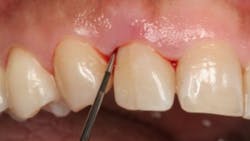

So, if the AAP guidelines are not a new way of diagnosing periodontal disease, how is it diagnosed and what are the possible diagnoses? To establish a diagnosis, we still need to perform a comprehensive periodontal examination, charting, and radiographs. Once the data is gathered and a diagnosis of periodontitis has been established, then the data can be interpreted within the framework of the staging and grading system to better describe the disease.

The possible diagnoses are health, gingivitis, or periodontitis. That’s it. Establishing the diagnosis is quite simple. If there is any level of bone loss, the patient has periodontitis. If there is no bone loss but there is bleeding on probing (BOP), the patient has gingivitis. If all sulci are 1–3 mm with no BOP, redness, or swelling, the patient is healthy.